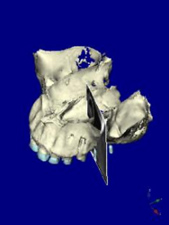

術前CT 1

第二小臼歯部

インプラントをシミュレーション